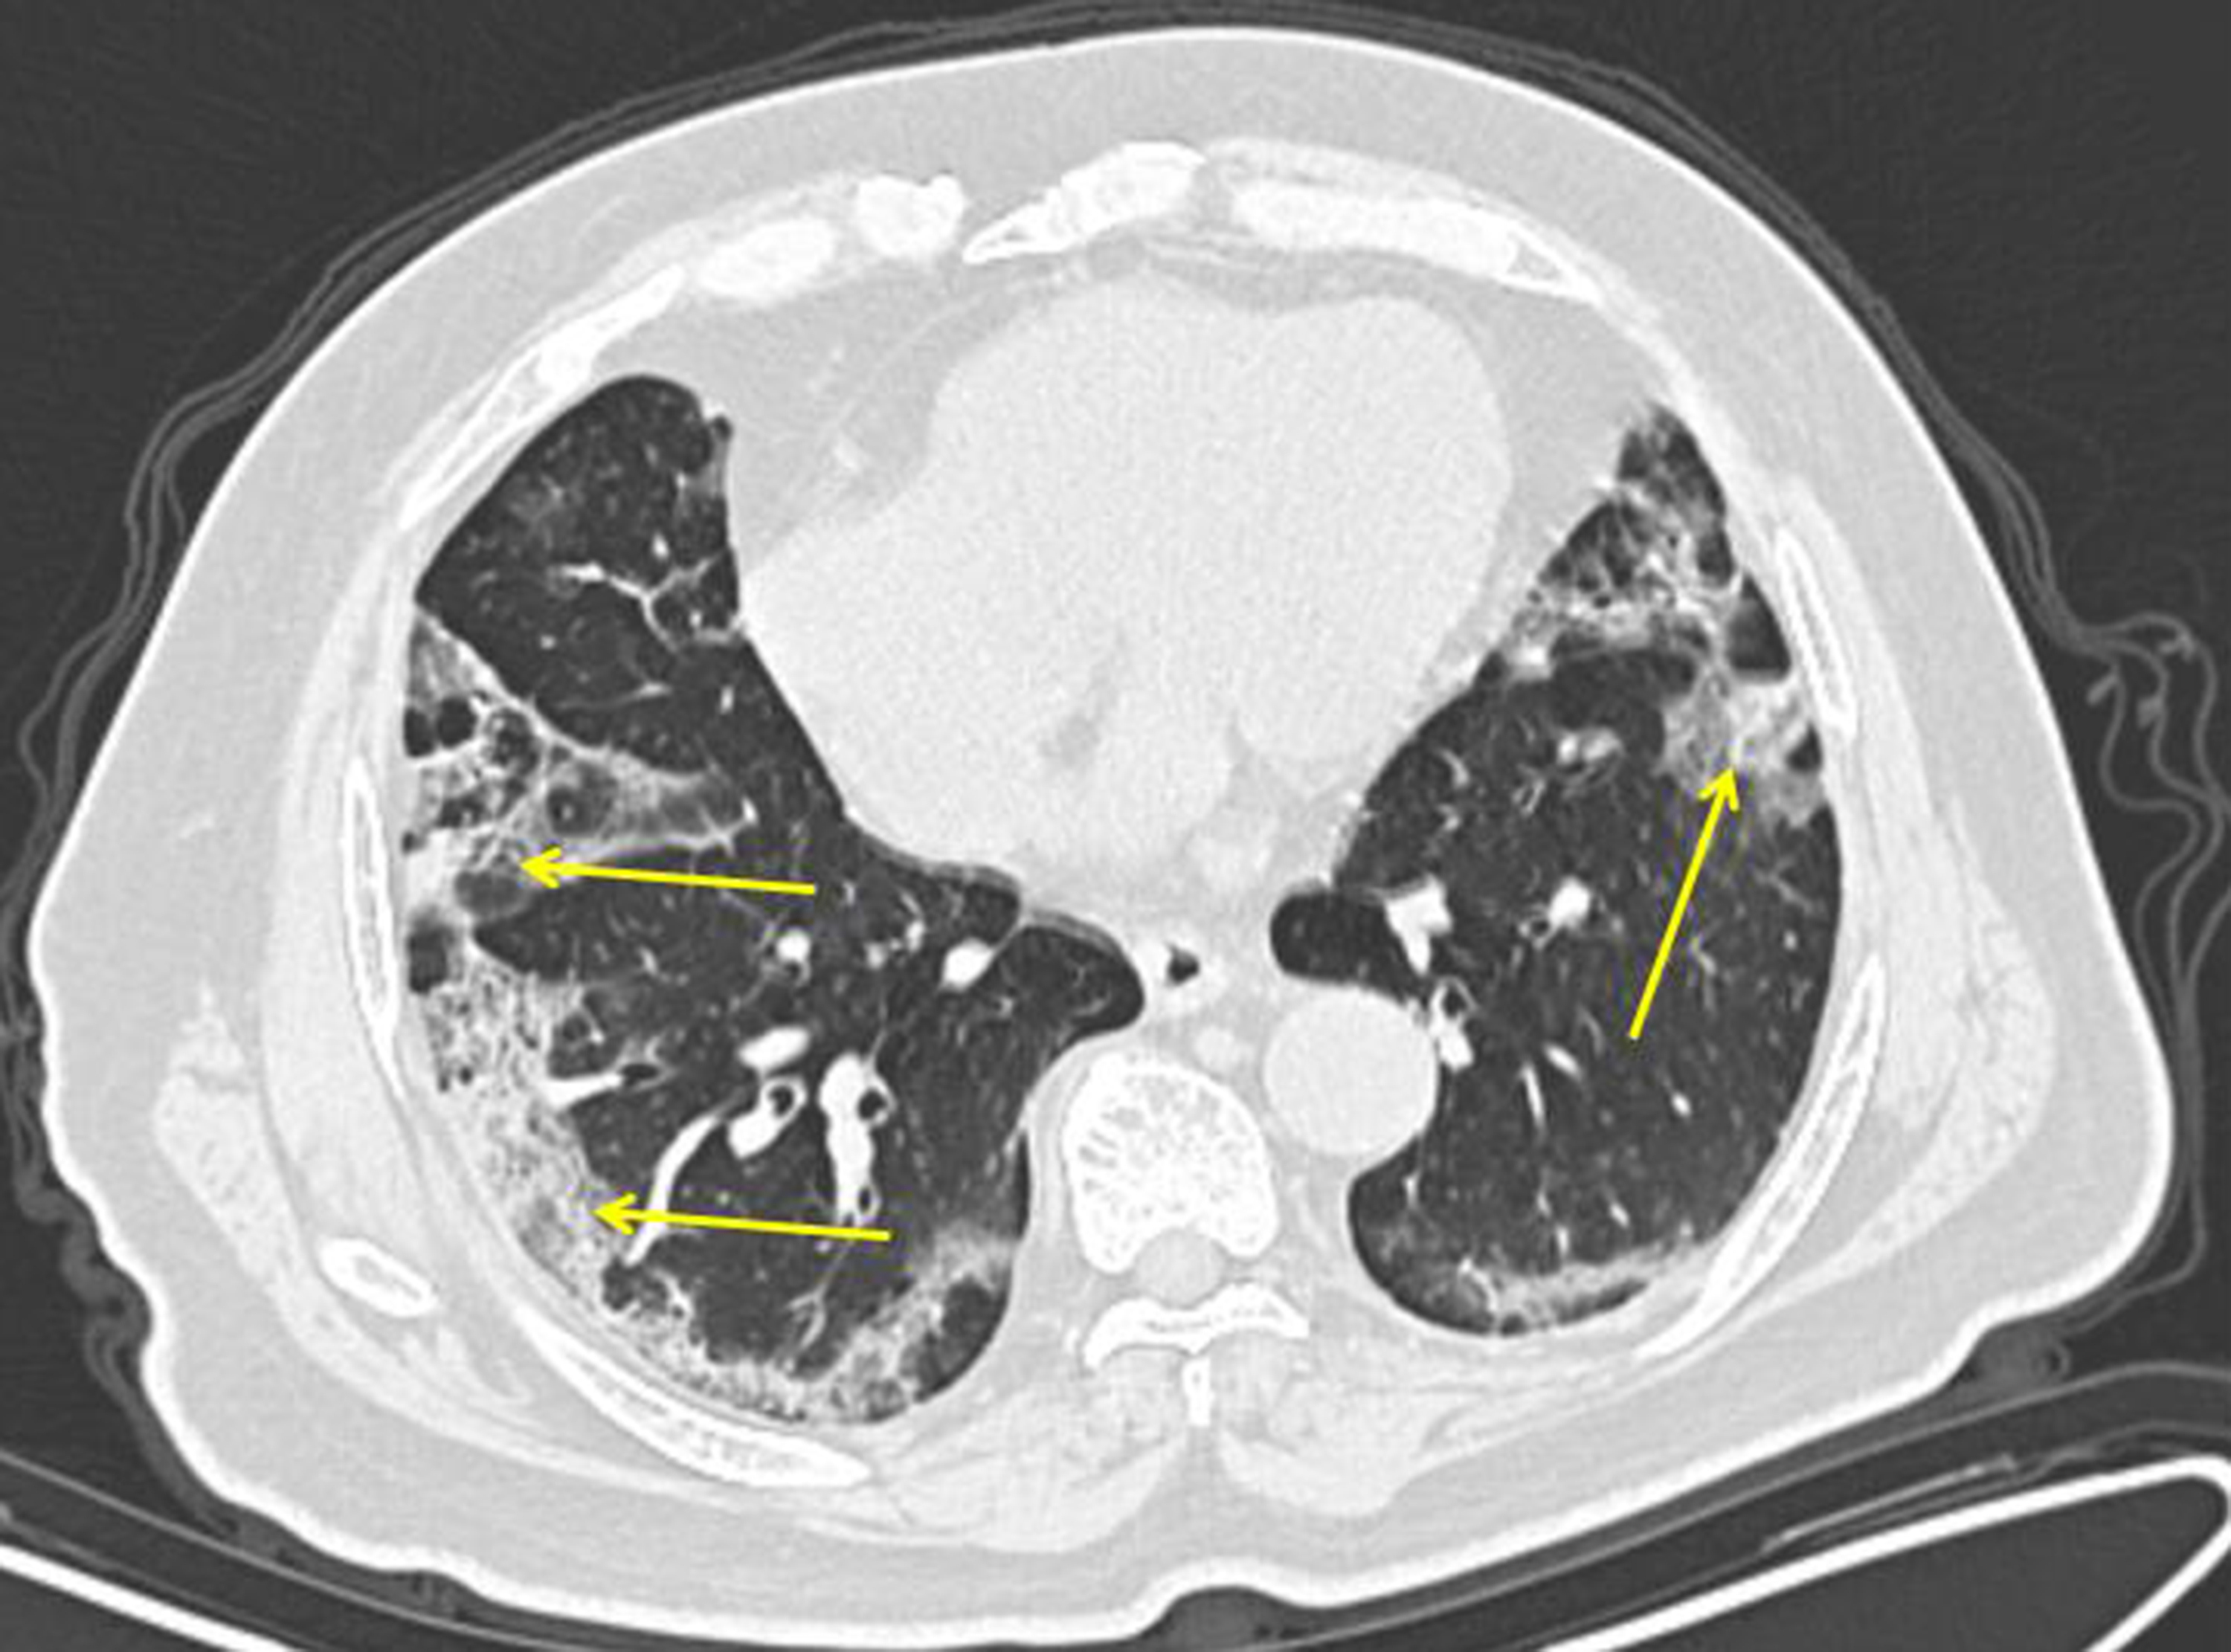

Chest Ct Images Of Covid 19 Lung Involvement In A 44 Year Old Huanan Seafood Worker Day 13 Of Symptom Progression Died 7 Days Later Covid19